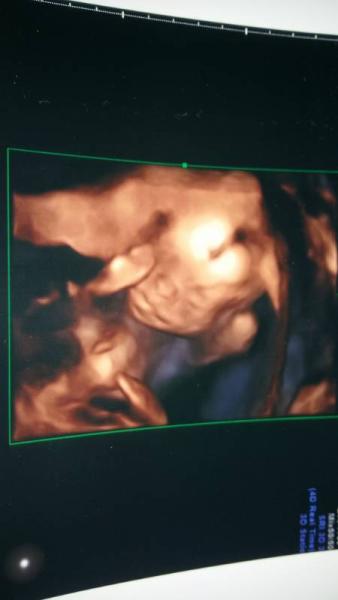

Alles Tip top..Unser Mäusschen ist 24,5cm und wiegt 400 gramm...Ich habe insgesamt knappe 2 Kilo zugenommen. Wir sind definitiv im Team rosa Am 26.3 muss ich in die Klinik zum Feinultraschall (wegen meinem Alter) Liebe Grüße, Naddel.

Bild zu Zurück vom 2ten großen US! - Forum für Juli - Mamis